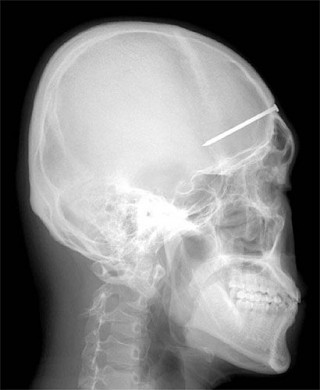

NAIL IN SKULL posted on June 9, 2014 by FireSafe Cambodia | Leave your thoughts Next image »« Previous image